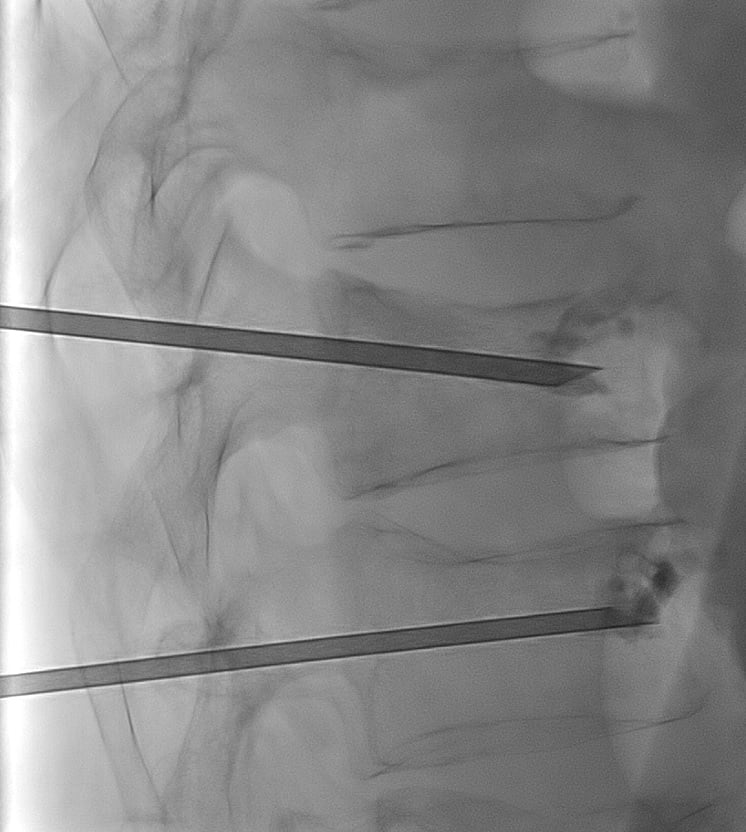

A l’aide d'un guidage radiologique par radiographie ou scanner, le médecin Radiologue Interventionnel va positionner une aiguille de vertébroplastie à travers la peau directement au sein de la vertèbre à traiter.

Le ciment est en suite injecté à travers l'aiguille jusqu'au bon remplissage de la vertèbre. L'injection est surveillée par les images de radiographie pour éviter les fuites de ciment.

Cimentoplastie percutanée réalisée dans notre centre : Photo 1 : aiguilles en place dans chaque vertèbre fracturée. Photo 2 : injection du ciment visible en radiographie (têtes de flèches bleues).